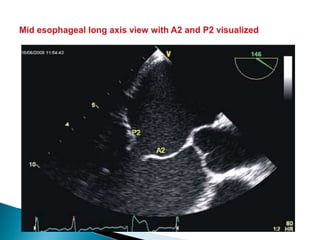

 The mitral valve is so named due to its appearance that resembles

a bishops’ miter.

 Trans esophageal echocardiography and the mitral valve (that sits

only 5–10 cm from the transducer with nothing but blood between

them)

 The posterior leaflet has clefts that divide it into 3 scallops (P1, P2, and P3);

 The anterior leaflet has no such scallops, but is described as having three regions that reflect

those of the posterior leaflet (A1, A2, and A3 respectively).

 In addition to the points of apposition along the leaflets, there are anterior (adjacent to A1/P1)

and posterior (adjacent to A3/P3) commissures.

 The non leaflet apparatus consists of the saddle-shaped mitral annulus, the chordae

tendinae (primary chordae attached to the free edges of the leaflets, secondary and tertiary

chordae attached to body of leaflets), and papillary muscles (anterior: chordae attached to

lateral aspects of leaflets; posterior: chordae attached to medial aspects of leaflets).